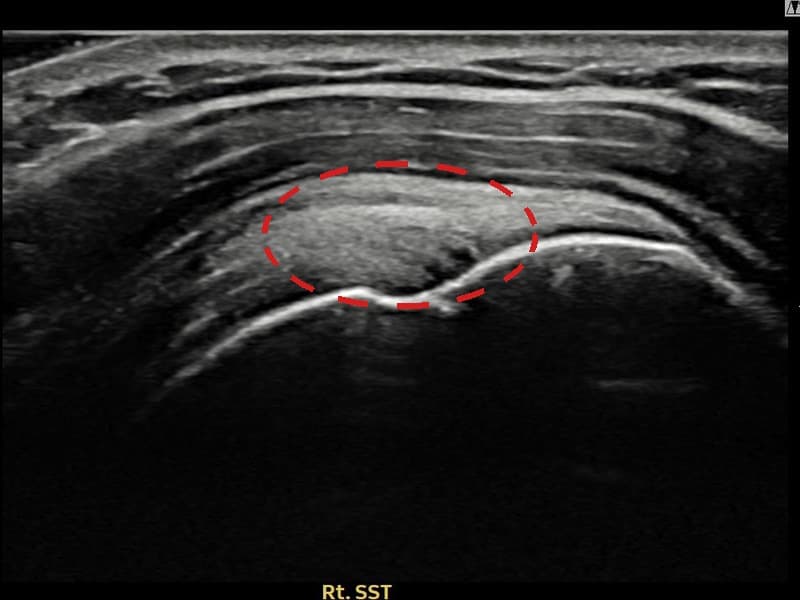

시술 전 초음파 측정 결과 파열 크기는 7mm × 4mm (힘줄 두께의 약 42% 결손)로 확인되었습니다. 시술 전 초음파에서 우측 극상근건 관절면측의 에코 단절과 힘줄 내부 결손 소견이 명확히 관찰되었으며, 힘줄 두께가 반대측 대비 현저히 감소된 상태였습니다. 시술 후 초음파에서 극상근건의 연속성이 회복되고 내부 에코 패턴이 균질하게 개선되어 파열 부위의 구조적 재생이 확인되었습니다.

50대 중반 여성 환자분으로, 꽃꽂이 강사로 활동하시며 팔을 앞·위로 반복적으로 뻗는 동작을 오랫동안 해오신 분이었습니다. 처음에는 수업 중에만 통증이 있었으나 점차 머리 감기, 선반 정리 등 일상 동작에서도 불편감이 생겨 내원하셨습니다. 초음파 검사에서 우측 극상근건 관절면측의 부분파열이 확인되었으며, 파열 범위와 위치를 고려해 초음파 유도 하 축소봉합술을 시행하였습니다. 시술은 30분 이내에 완료되었고 당일 귀가하셨으며, 시술 후 4주간 팔을 어깨 위로 올리는 동작을 제한하고 단계적으로 가동 범위를 늘려 나갔습니다. 시술 13주 후 추적 초음파에서 극상근건 연속성이 완전히 회복되고 에코 패턴이 정상화된 것이 확인되었으며, 통증 없이 강의에 복귀하셨습니다.